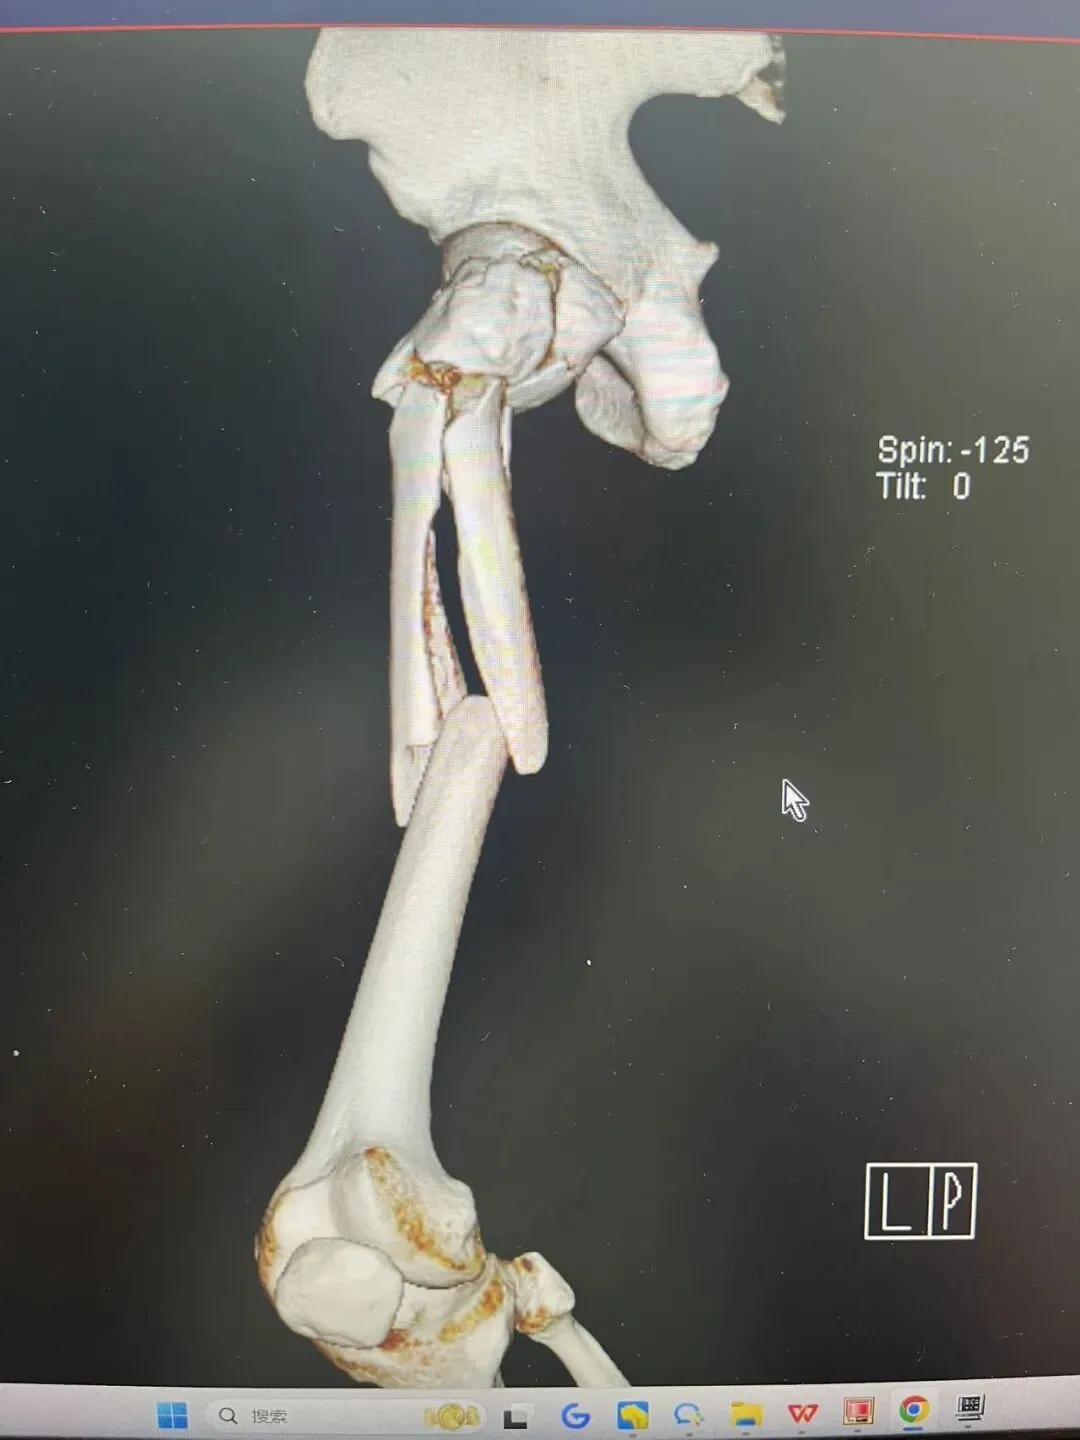

再看看在门诊看到的外院一例相似患者,

为了复位骨折而复位骨折的切开做,当然切开没有绝对的错,早期没有髓内钉的时候,我们也切开做,但这样的切开,就没有创伤骨科理念。

术后2月,远端锁钉都退了。